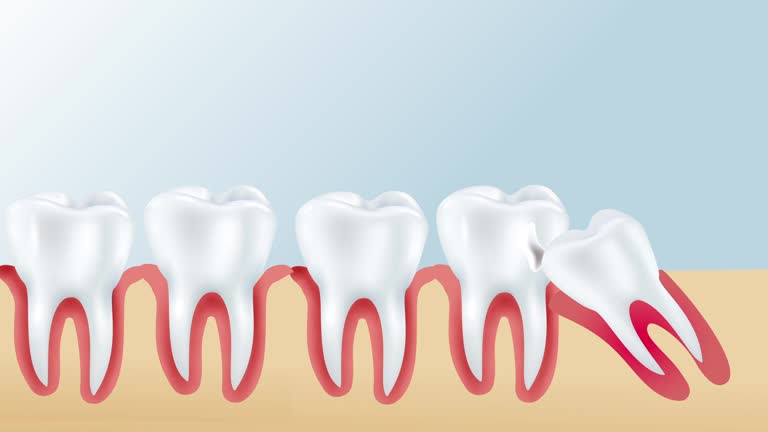

Impacted wisdom teeth can cause several types of harm when they grow later.

1. When impacted wisdom teeth grow, they injure adjacent teeth. The dental nerve becomes infected and inflamed, causing severe pain. The dental nerve dies, and the periodontium may be sealed.

2. When impacted wisdom teeth grow, the roots of adjacent teeth are squeezed and broken, and the dental nerves become infected and inflamed, causing severe pain. The adjacent teeth cannot be reworked and can only be extracted.

3. A deep blind pocket will be formed between the impacted wisdom teeth and the surrounding gums, which can easily cause food residues to stick to the tooth surface, thereby accumulating for a long time, gradually forming bacterial infection, and deep caries can reach Deep in the dentin, close to the pulp, or may have affected the pulp, causing severe pain.